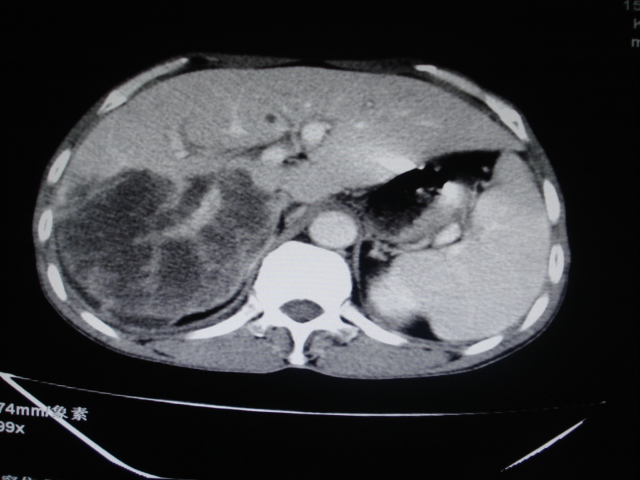

标题: CT24041:肝脏占位,请会诊!

男性,62岁。肝右叶占位,平扫及增强如下,延迟期为15分钟扫描。

给病史及实验室检查!多考虑胆管细胞癌;右肾囊肿。

1)不均匀性脂肪肝。2)肝硬化。3)肝右叶肝癌不排除。4)右肾囊肿。